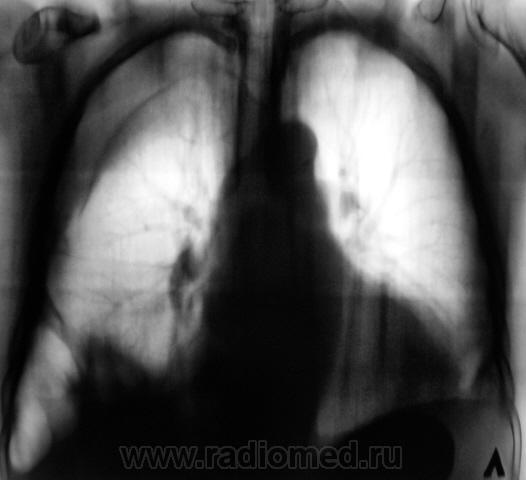

Следующий случай.

Литические Mts

А, ежели метастазы полностью исключаются, тогда как?

миеломная болезнь?